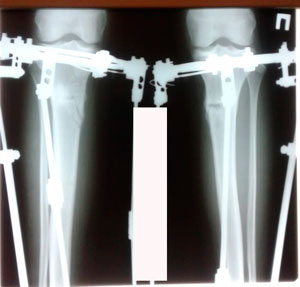

84 дня.

Пора на снятие аппаратов!!!

84 дня с момента операции.

Дата операции - 16.10.2019г.

Дата снятия аппаратов - 16.01.2020 г.

Срок сращения - 90 дней